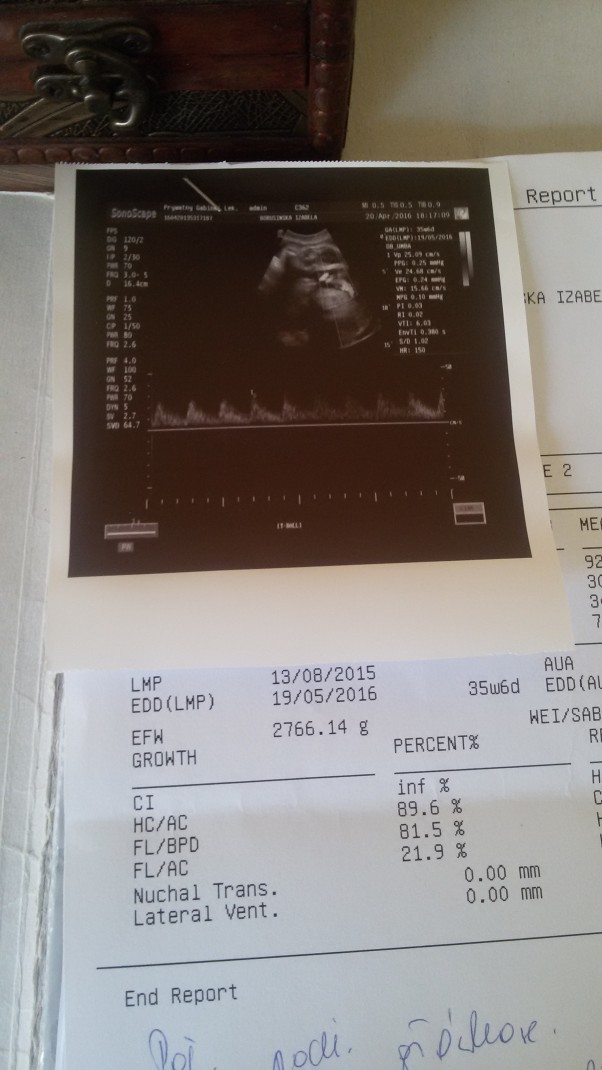

Kolejna wizyta u lekarza i kolejne dobre wiadomości. Maluszek rośnie i przybiera na wadze. Serduszko bije równo miarowo. Tylko już bardzo dużo waży;)